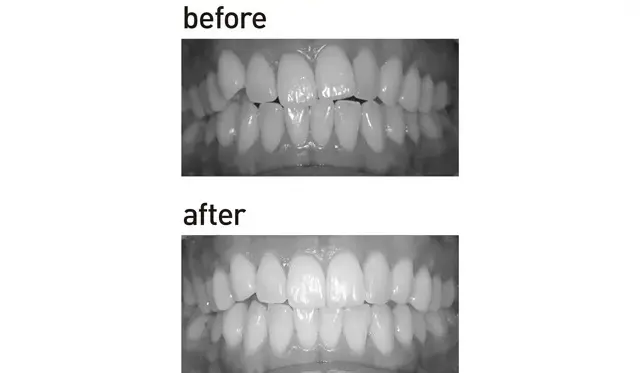

奥歯4本ずつの銀歯をセラミックに変え、前歯には裏側ワイヤー矯正も。人に見せたくなる仕上がりに